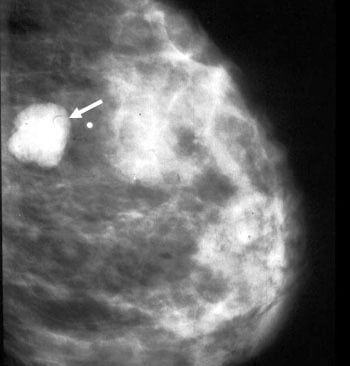

Mamografi (Altın Standart):

Mikrokalsifikasyonlar: LR (+) 15.0. (Özellikle pleomorfik/dallanan tipteyse)

Spiküle Kitle: LR (+) > 20.0.

Meme Ultrasonografisi (USG):

Dens memelerde (Genç hastalar) mamografinin kör noktalarını aydınlatır.

Solid vs Kistik ayrımı: Kist ise LR 0 (Benign), Solid ve damarlanma artışı varsa LR (+) 10.0.

"Mamografide Spiküle (Dikenli) Kitle Varlığı ile Luminal A Alt Tip Meme Kanseri Arasında Bir Korelasyon Var mıdır?"

Bu çalışma, mamografik görüntüleme bulguları ile meme kanserinin moleküler alt tipleri arasındaki biyolojik bağı incelemektedir. 317 hastanın retrospektif analizi üzerinden yapılan çalışma, fenotip (görüntü) ile genotip (moleküler belirteçler) arasındaki ilişkiyi Bayesyen bir olasılık çerçevesinde sunar.

Luminal A Dominansı: Spiküle (kenarları ışınsal uzantılı) kitlelerin %71'i Luminal A alt tipi olarak sınıflandırılmıştır.

Olasılık Oranı (Odds Ratio): Luminal A alt tipindeki kitlelerin, diğer alt tiplere oranla mamografide spiküle görünüm sergileme olasılığı 10.3 kat daha fazladır (p < 0.001).

İyi Prognoz İşareti: Spiküle marjlar, genellikle tümör hücrelerinin çevre dokuyla (stroma/yağ dokusu) etkileşimini ve düşük dereceli (low-grade) progresyonu gösterir. Bu durum, spiküle kitlelerin neden daha iyi bir prognoza işaret ettiğini açıklar.